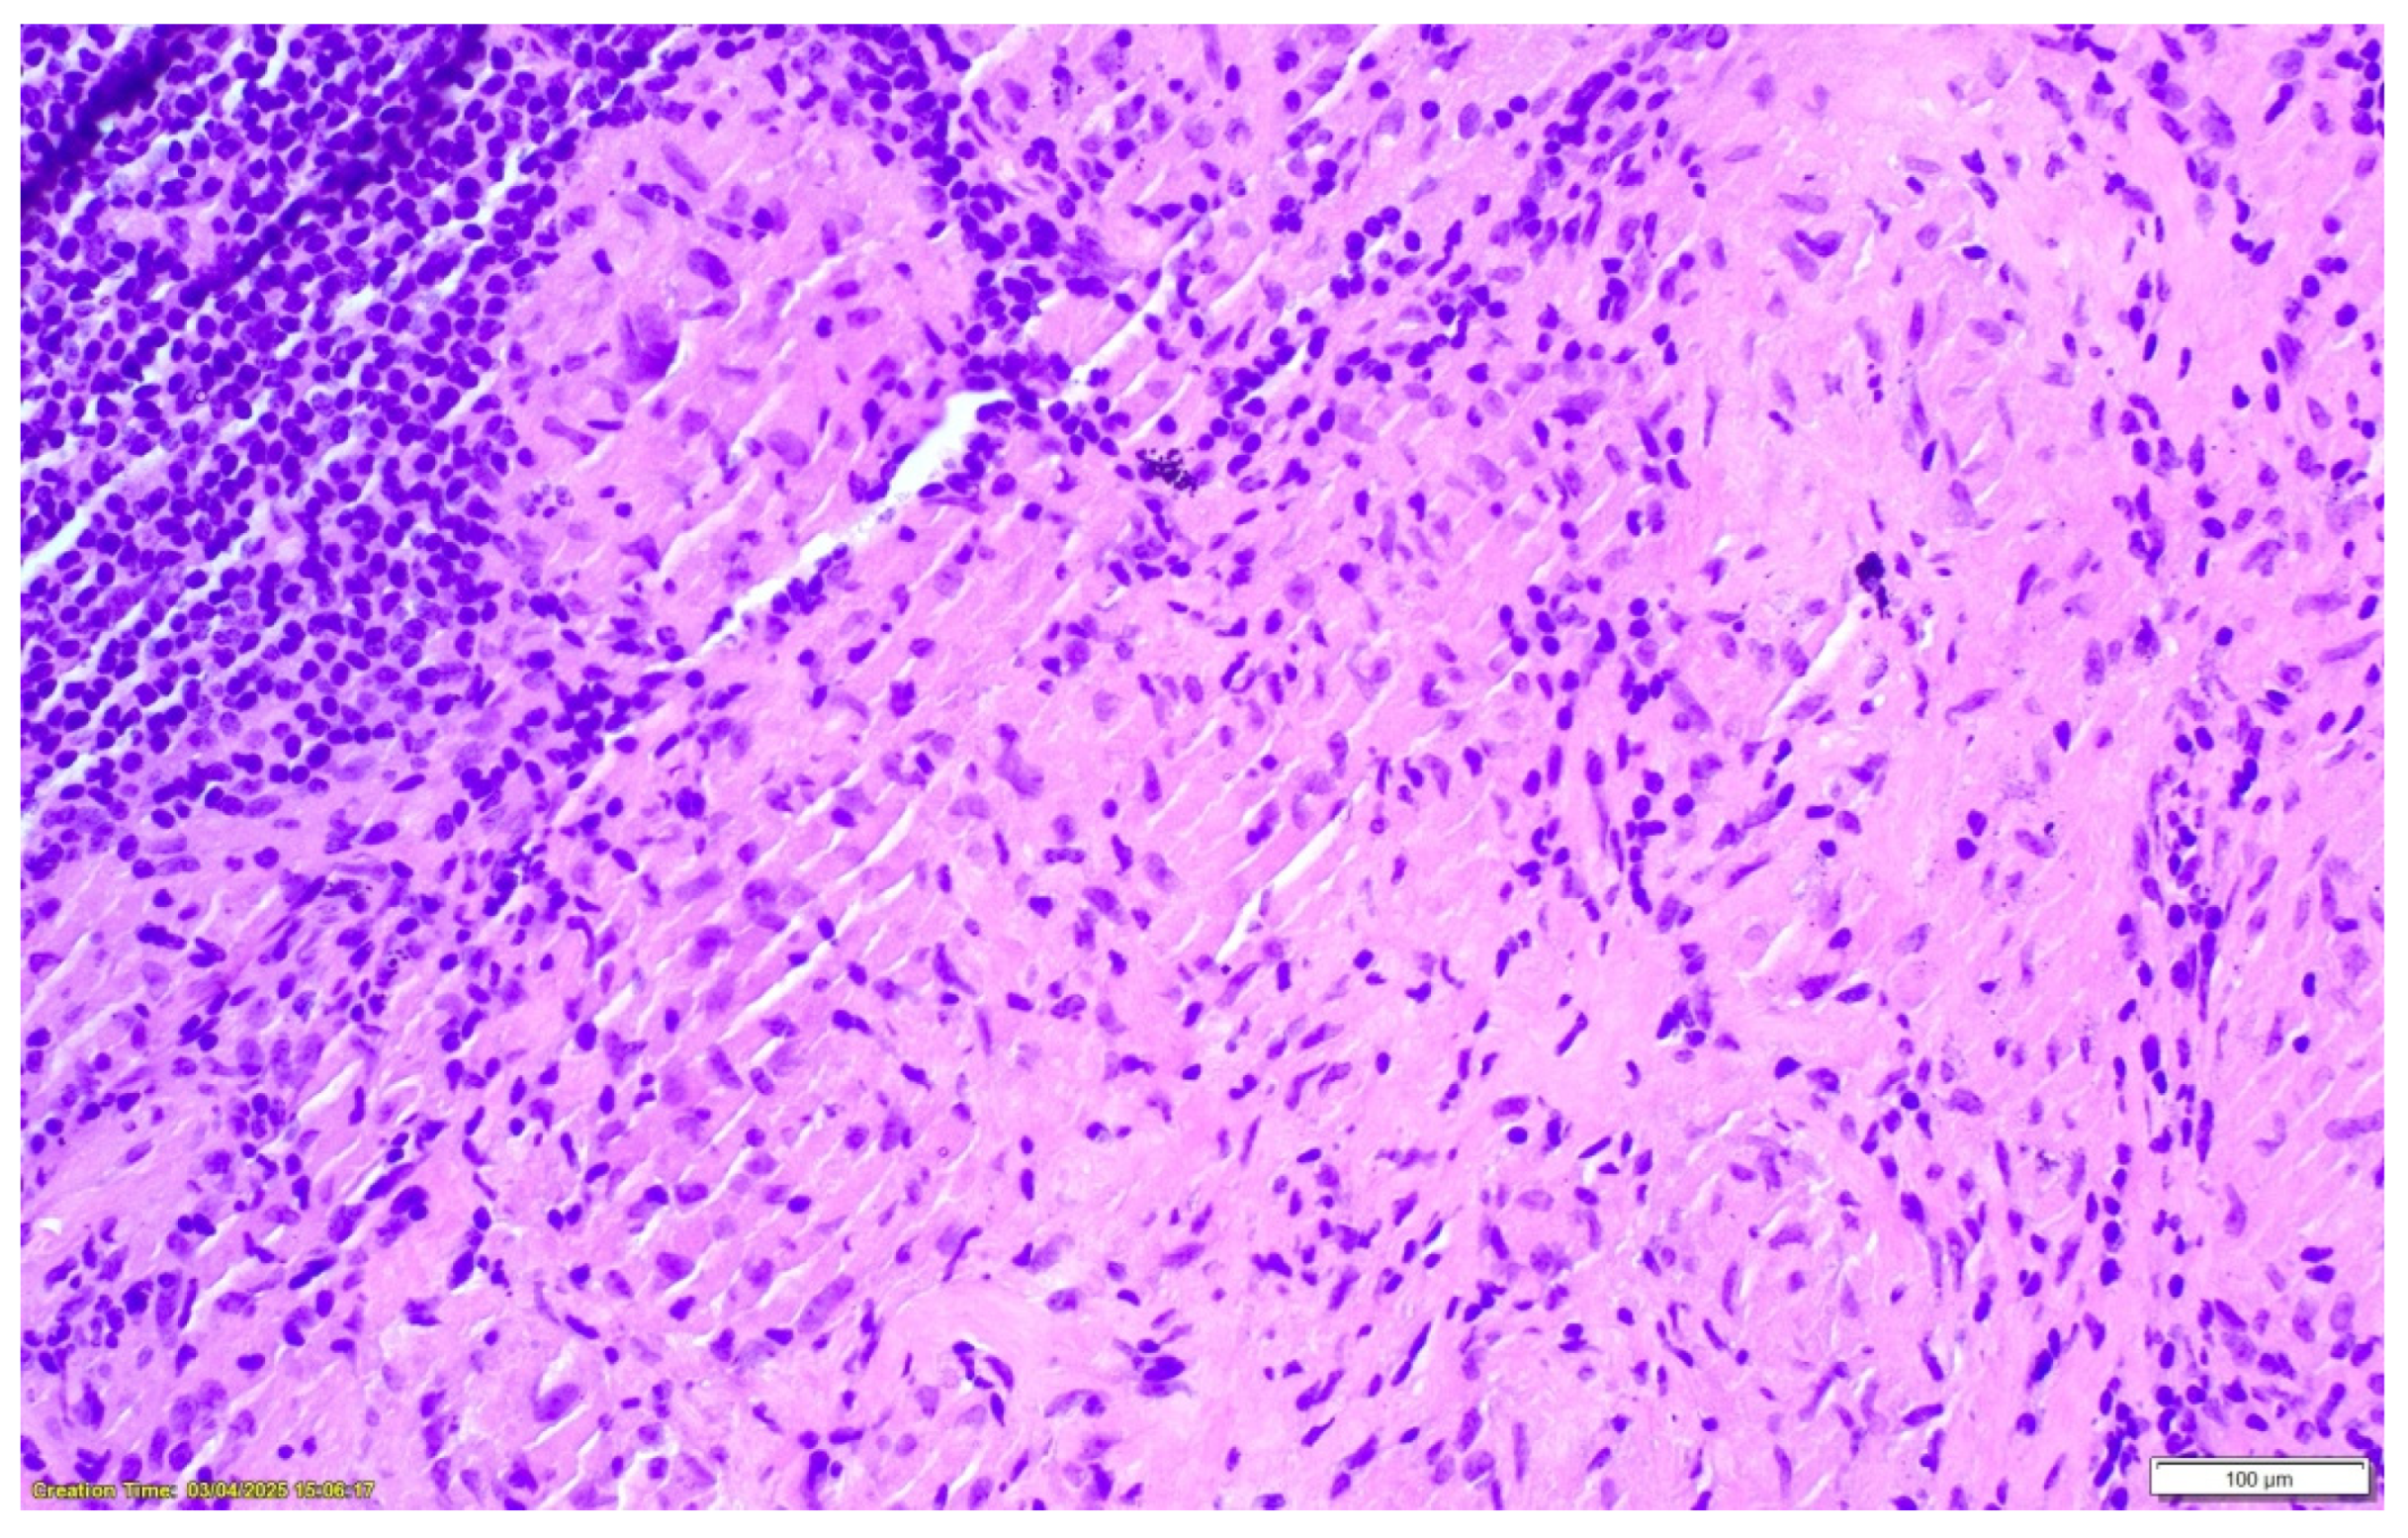

2. Case Presentation